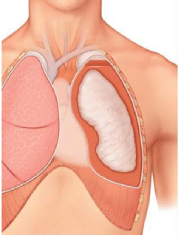

Decortication is a surgical procedure that removes a restrictive layer of fibrous tissue overlying the lung, chest wall, and diaphragm. The aim of decortication is to remove this layer and allow the lung to reexpand. When the peel is removed, compliance in the chest wall returns, the lung is able to expand and deflate, and patient symptoms improve rapidly.